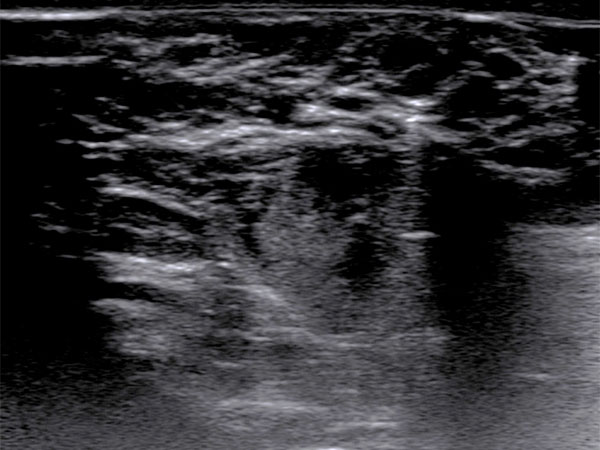

To confirm the diagnosis, an ultrasound-guided punch biopsy was now taken from the lesion on the right labium majus using a 16-gauge disposable biopsy gun. The biopsy needle advanced into the lesion produces strong distal acoustic shadowing on B-scan imaging.